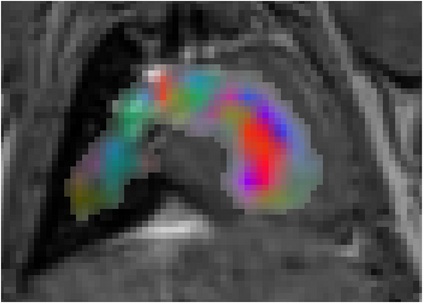

Various imaging modalities allow for time-dependent image reconstructions from measurements where its acquisition also has a time-dependent nature. Magnetic particle imaging (MPI) falls into this class of imaging modalities and it thus also provides a dynamic inverse problem. Without proper consideration of the dynamic behavior, motion artifacts in the reconstruction become an issue. More sophisticated methods need to be developed and applied to the reconstruction of the time-dependent sequences of images. In this context, we investigate the incorporation of motion priors in terms of certain flow-parameter-dependent PDEs in the reconstruction process of time-dependent 3D images in magnetic particle imaging. The present work comprises the method development for a general 3D+time setting for time-dependent linear forward operators, analytical investigation of necessary properties in the MPI forward operator, modeling aspects in dynamic MPI, and extensive numerical experiments on 3D+time imaging including simulated data as well as measurements from a rotation phantom and in-vivo data from a mouse.